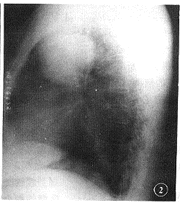

X线与CT表现:右上肺类圆形包块大小约8 cm×6 cm×7 cm,密度均匀,边缘光滑,周围肺 野与肺门及纵隔未见异常(图1,2)。

图1,2 X线表现:右肺中上野见约8 cm×6 cm×7 cm球形肿块,密度均匀,边 缘光滑, 周围骨性结构未见侵蚀破坏征象, 百拇医药